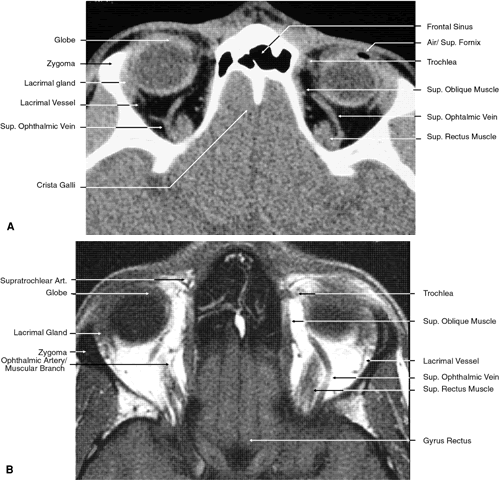

The globe is shown in Figure 12. The orbit and periorbital structures are shown in Figures 13 through 16, and the optic canal is shown in Figures 17 through 26. The cavernous sinus and optic chiasm are shown in Figures 27 and 28, and the posterior visual pathway and cranial nerves are shown in Figures 29 through 33.

Fig. 17. Coronal images through anterior orbit. A. Computed tomography scan. B. T1-weighted magnetic resonance imaging.

Fig. 18. Coronal images through midglobe. A. Computed tomography scan. B. T1-weighted magnetic resonance imaging.

Fig. 19. Coronal images through midorbit posterior to the globe. A. Computed tomography scan.B. T1-weighted magnetic resonance imaging.

Fig. 20. Coronal images through orbital apex. A. Computed tomography scan. B. T1-weighted magnetic resonance imaging. C. Anatomic section of a cadaver head at the level of the orbital apex.

Fig. 21. Coronal images through optic canal. A. Computed tomography scan. B. T1-weighted magnetic resonance imaging.

Fig. 22. Axial images at the level of inferior orbit. A. Computed tomography scan. B. T1-weighted magnetic resonance imaging.

Fig. 23. Axial images at the level of midorbit. A. Computed tomography scan. B. T1-weighted magnetic resonance imaging.

Fig. 24. Axial images at the level of superior orbit. A. Computed tomography scan. B. T1-weighted magnetic resonance imaging.

Fig. 25. Axial images at the level of tendon of the superior oblique. A. Computed tomography scan. B. T1-weighted magnetic resonance imaging.

Fig. 26. T1-weighted magnetic resonance imaging; sagittal image through optic nerve.